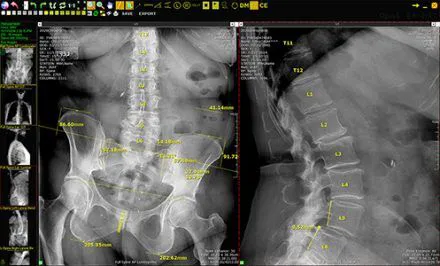

Chiropractic Adjustments: The practice provides advanced spinal correction using "state of the art" chiropractic techniques. Dr. Stein is highly experienced in various methods, including Atlas Orthogonal, a precise and gentle technique for the upper cervical spine, which is particularly effective for conditions like vertigo and migraines.